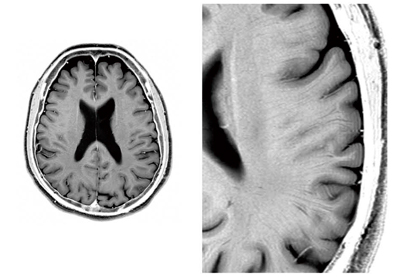

3T MRI画像例

図5に,頭部の高空間分解能T2強調画像を示します。拡大画像では,空間分解能が高いことで細かな髄質静脈まで描出されています。組織構造上の違いによる3T特有のコントラストを有する髄質静脈の描出は,病変の鑑別に有用と期待されています。

図5 3T MRI画像例:頭部,2DFSE T2WI